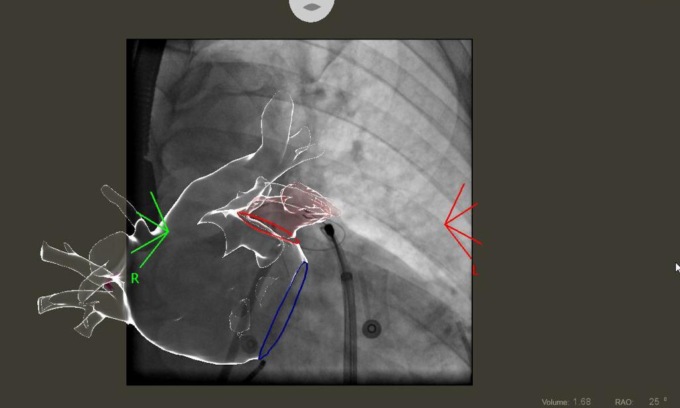

Un paziente torinese di 56 anni è stato sottoposto ad ablazione della fibrillazione atriale eseguita sia dall’interno sia dall’esterno del cuore (endo-epicardica) associata a legatura non chirurgica dell’auricola sinistra, presso la Cardiologia dell’ospedale Mauriziano di Torino (diretta dal dottor Giuseppe Musumeci).

E’ stata pertanto eseguita una ablazione della fibrillazione atriale sia tradizionale che attraverso la superficie esterna, epicardica, del cuore, mediante un approccio mini-invasivo non chirurgico associato ad una legatura esterna epicardica, ma non chirurgica della auricola sinistra. La procedura è stata effettuata in corso di sedazione superficiale.

La combinazione delle due tecniche, utilizzata per la prima volta al mondo, ha consentito di ripristinare un regolare ritmo cardiaco ed abbattere sensibilmente il rischio di ictus cerebrale senza la necessità di sottoporre il paziente a terapia anticoagulante o antiaggregante a lungo termine, evitando in questo modo episodi di sanguinamento.

L’ablazione eseguita sulla superficie esterna del cuore, definita epicardica, consente infatti di accedere ad aree aritmogene che non possono essere raggiunte mediante l’approccio tradizionale dall’interno del cuore a causa dello spessore della parete cardiaca, migliorando di molto i risultati della procedura ablativa.

La legatura epicardica della auricola sinistra, mai effettuata prima in Italia, consente di abbattere il rischio di ictus embolico legato alla fibrillazione atriale senza necessità di mantenere il paziente non solo in terapia anticoagulante, ma se richiesto anche in terapia antiaggregante. A differenza di tutti i sistemi utilizzati in precedenza infatti, questa metodica non prevede l’inserimento di alcun dispositivo permanente all’interno delle camere cardiache. Inoltre determina una esclusione anche elettrica della auricola che migliora ulteriormente il risultato dell’ablazione.